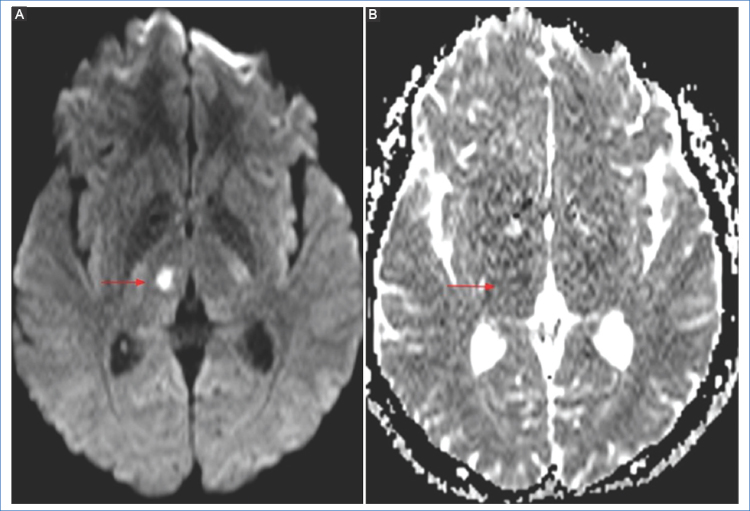

Luego de la oclusión vascular comienza una cascada de eventos, como la falla de la bomba de sodio y potasio, aumento del calcio intracelular, despolarización celular, generación de radicales libres, inflamación y apoptosis, produciendo edema intracelular (citotóxico) y disminución del movimiento browniano de los líquidos4. Dentro de la evaluación del parénquima cerebral, la secuencia DWI y el mapa de coeficiente de difusión aparente (ADC, por sus siglas en inglés), son las que presentan mayor sensibilidad para la detección de isquemia parenquimatosa, con una sensibilidad del 88-100% y especificidad del 95% para detectar el core del infarto, en relación con la TC5,6, aunque hay un pequeño número de pacientes en los cuales no se observan alteraciones (stroke DWI-negativo)6. La anormalidad de señal en la secuencia DWI (representando el edema citotóxico) se observa hiperintensa y corresponde a una restricción en la difusión normal de la molécula de agua dentro del parénquima encefálico, con la equivalente reducción de los valores de ADC (hiposeñal). Esto representa signos de lesión irreversible y corresponde al core del infarto7 (Fig. 1). La reducción de los valores del coeficiente de difusión en el mapa de ADC pueden observarse a los 30 minutos luego del comienzo de la isquemia, alcanzando valores más bajos alrededor de los 3-5 días. Luego los valores de ADC comenzarán a incrementarse, hasta alcanzar una pseudonormalización alrededor de las 2-4 semanas, debido al mayor componente vasogénico del edema, en vez de citotóxico (efecto T2 shine through)2,7.

Algunos autores sugieren que un valor bajo del coeficiente de ADC menor a 550 × 10−6 mm2 es un predictor independiente de transformación hemorrágica luego de la trombólisis 9,10 (Fig. 2).